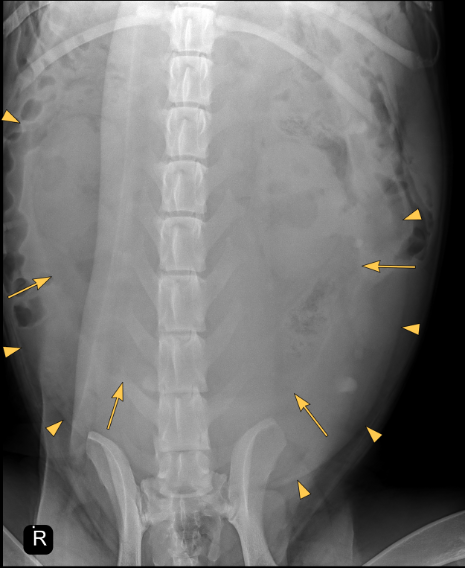

There is severe distention of the abdomen. As far as included the extra-abdominal soft tissues are within normal limits. There are 8 lumbar vertebrae, otherwise the bony structures are within normal limits.

A large well-defined, rounded soft tissue mass is noted in the caudal mid and cranial abdomen. The mass is filled with combination of fluid ( yellow arrow points) and gas (yellow arrows) and originating from the uterus.

The mass is displacing the gastrointestinal tract dorsally, cranially and laterally.

Large fluid and gas-filled mass in the caudal, mid and cranial abdomen originating from the uterus (emphysematous pyometra). Considering the shape of the mass a torsion is suspected.